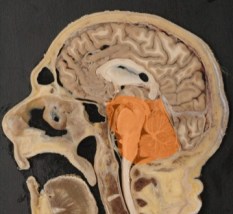

les compartiments intra-crâniens

compartiments anatomiques

la cavité crânienne est cloisonnée par des replis de dure-mère, la faux du cerveau et la

tente du cervelet, qui délimitent :

- la cavité hémisphérique droite

- la cavité hémisphérique gauche

- la fosse postérieure

compartiments physiologiques

on distingue parmi les composants intracrâniens, les compartiments :

- tissulaire, lui-même composée de compartiments :

- intra-cellulaire

- extra-cellulaire

- vasculaire, réparti en compartiments :

- artériel et artériolaire

- capillaire

- veineux

- liquidien, comprenant le liquide cérébro-spinal

- ventriculaire

- cisternal

- des espaces périvasculaires de Virchow-Robin